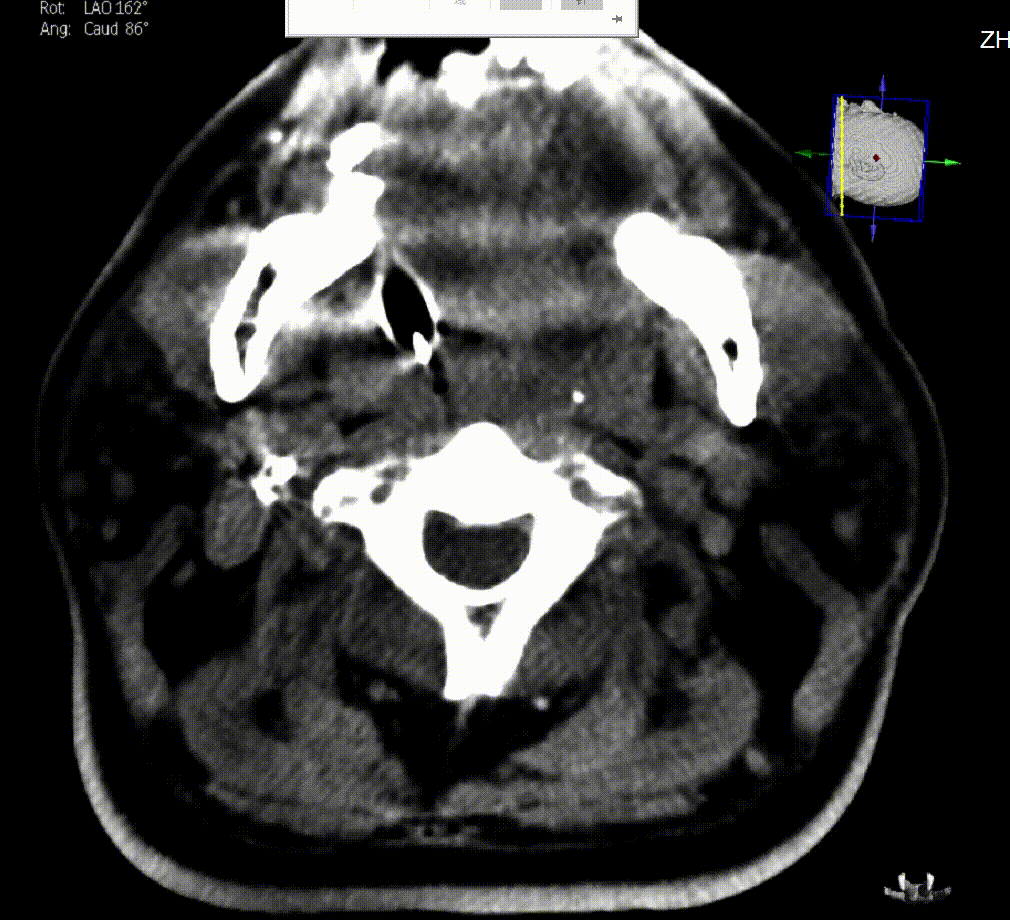

图4. 右侧颈内动脉造影提示胚胎型后交通动脉

综合术前辅助检查,(Core+pen)/Core=3.58;Pen>15ml;Core<70ml(图3);发病时间小于24小时,存在取栓指征,但是当地医院手术经验告诉我们左侧椎动脉慢性闭塞,且开通异常困难,常规手术方案很难成行,术前制定合理且可行的手术方案至关重要。方案1:仍采用左侧椎动脉+基底动脉取栓的正向开通方案,可能会继续浪费大量时间,甚至最后以失败告终。方案2:采用右侧椎动脉入路,由于右侧椎动脉V4段发育不良,当地医院已尝试过超选,证实无法通过V4段至基底动脉建立取栓通路。方案3:既往有文献报道开颅椎动脉直视下穿刺取栓,虽然方案可行,但我院无类似手术经验,贸然尝试风险难以把控。方案4:回顾当地医院取栓影像资料,发现双侧颈内动脉后交通呈胚胎型,是否可能通过后交通跨循环逆向超选至基底动脉取栓。患者平卧DSA床,全麻插管成功后,用碘伏常规消毒手术区皮肤,铺无菌巾单。取双侧股动脉为穿刺点,于14时00分seldinger法穿刺成功后分别置入8F穿刺鞘和5F 短鞘。行全脑血管造影显示左侧椎动脉起始部闭塞,颈升动脉通过肌支代偿V2及以远的椎动脉血流,右侧椎动脉V4段发育不良,单纯供应右侧PICA,双侧后交通动脉胚胎型。(图9,图10)首先我们仍尝试传统入路进行超选左侧椎动脉,发现左侧椎动脉开口闭塞,斑块质地坚硬,微导丝微导管无法通过。短暂尝试无果后,迅速改为右侧椎动脉入路,发现将微导丝塑型成“J”型或成袢,均无法到达右侧椎动脉V4段,遂果断决定采用跨循环取栓方案。将5F VERT造影导管超选至左侧锁骨下动脉,进行正向血流监测。6F 90cm长鞘(cook)及5F 125cm Navien导管在泥鳅导丝带领下超选进入右侧颈内动脉岩骨段。随后将Rebar18微导管在Synchro2微导丝带领下超选至大脑中动脉,并将Navien带领至右侧颈内动脉交通段。微导丝微导管回撤至颈内动脉,路图下Synchro2微导丝带领Rebar18逐步通过右侧后交通动脉,再在透视下经右侧大脑后动脉P1段盲超选至基底动脉下段。(图11-13)手推造影确认Rebar18微导管已突破血栓段,并在基底动脉真腔内。(图14)经Rebar18释放一枚solitaire FR支架(4mm×20mm)覆盖血栓段。SWIM技术负压下抽拉支架1次,抽拉过程中时刻注意系统张力,逐步回撤支架同时适度回撤Navien释放张力,以保证Navien贴近后交通开口而不向后交通动脉内继续深入。撤出支架后,Navien原位保持负压约30秒。(图15)造影复查见基底动脉及其分支再通,支架取出少量血栓(图18)。于14时45分达到远端血流mTICI3级,10分钟后复查造影显示血管通畅,于14时55分末次造影见远端血流维持mTICI3级。(图16,17)术中Dynamic CT未见明显术区出血(图19)。遂缝合穿刺点,结束手术。手术顺利,术中病人情况稳定。术末血压115/58mmHg,脉搏70次/分,呼吸12次/分,氧饱和度100%。术毕送重症监护室。图9. 双侧椎动脉造影:左侧椎动脉起始部闭塞,左侧颈升动脉肌支和右侧椎动脉通过脊髓支代偿V2及以远的椎动脉血流;右侧椎动脉V4段发育不良,单纯供应右侧PICA

图10. 右侧颈总动脉造影:后交通动脉胚胎型